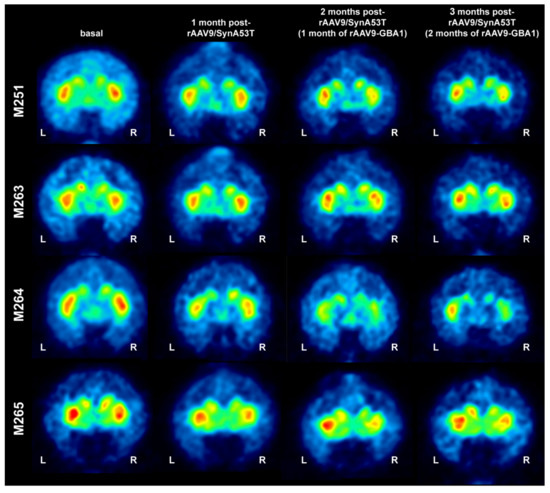

2.2.1. MicroPET Neuroimage Studies

4.3.2. MicroPET Scans